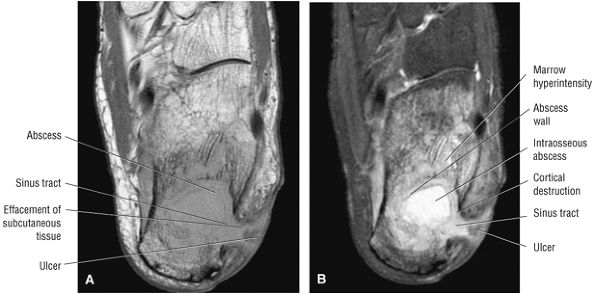

Thickening (Fig. 5.180) or absence of the ligament in acute injury

-

Subacute to chronic residual thickening in a healed and scarred ligament (Fig. 5.181)

Chronic instability associated with attenuated or hypoplastic ligament with sharper, more defined ligament margins